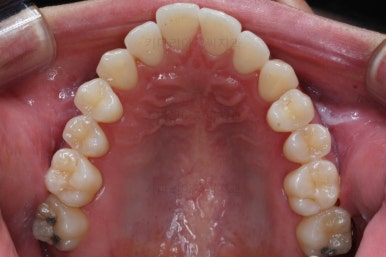

부산비수술교정 키다리아저씨치과에 처음 내원하셨을 당시의 입 안의 모습입니다.

아래 앞니에 결손치아가 하나 있네요. 송곳니-송곳니 사이에 앞니가 4개가 있어야 정상이지만 이 분은 3개에요. 의외로 아래앞니 하나 혹은 두개가 없는 경우가 굉장히 많답니다.

갯수가 맞지 않다보니 치열의 중앙도 맞지 않고 비대칭이 됩니다.

그리고 주걱턱이기 때문에 당연히 아랫니들도 앞으로 나올 수 밖에 없어 윗니보다 앞에 나와있어요.

이를 반대교합이라고 합니다.

어금니의 맞물림도 연쇄적으로 몇 칸씩 밀려있는 양상이라 효율도 좋지 못하고 치아의 건강에도 좋지 못해요.

이 분의 경우에도 전반적으로 잇몸이 약해져있을 수 밖에 없어요. 보시면 아시겠지만 잇몸 퇴축이 심해서 치아들이 길쭉길쭉해 보이죠.